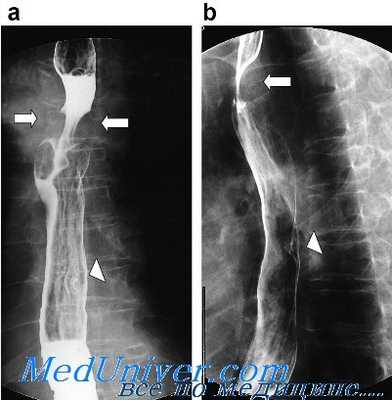

(Слева) При рентгенографии пищевода со взвесью сульфата бария определяется полная обструкция просвета и дефект наполнения - изменения, обусловленные проглатыванием недостаточно разжеванного куска мяса. После его извлечения у пациента было обнаружено кольцо Шацкого.

(Справа) При рентгенографии, выполненной ребенку в возрасте одного года, проглотившему батарейку от часов, в проекции шейного сегмента пищевода визуализируется большая округлая тень. Обратите внимание, что тень (в отличие от моменты с зазубренными краями) имеет ровные очертания. Поскольку батарейка обусловливала стойкое сужение просвета пищевода, потребовалось ее извлечение.